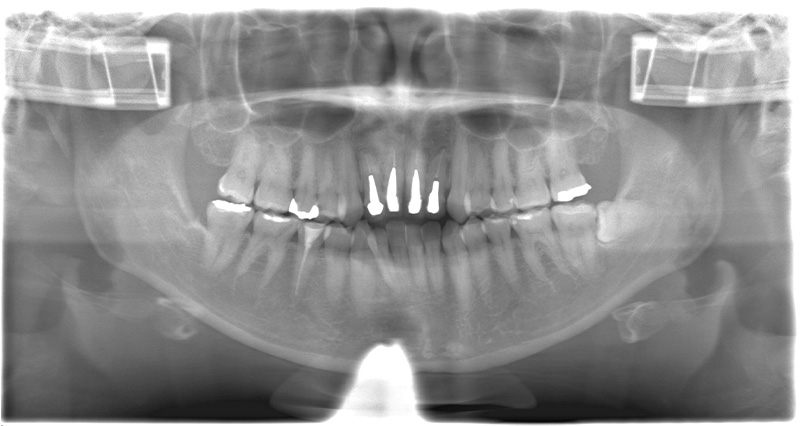

レントゲン、口腔内写真

セラミック治療を進めていく際には、患者様の目指しているゴールを明確にして、あとは根のコンディションがどうなのか?歯茎のコンディションはどうなのか?を考慮して、最終的なゴールを決めていきます。

- 口腔内写真撮影

- パノラマレントゲン撮影

- CT撮影